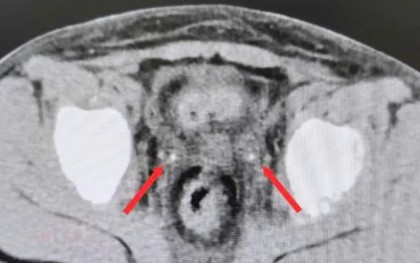

Cực kỳ hiếm: Sỏi niệu quản kẹt hai bên sau mổ viêm ruột thừa khiến bệnh nhi suy thận cấp

Bé trai 9 tuổi vô niệu, suy thận cấp do sỏi niệu quản kẹt hai bên sau mổ ruột thừa, được can thiệp khẩn, hồi phục chức năng thận ngoạn mục.